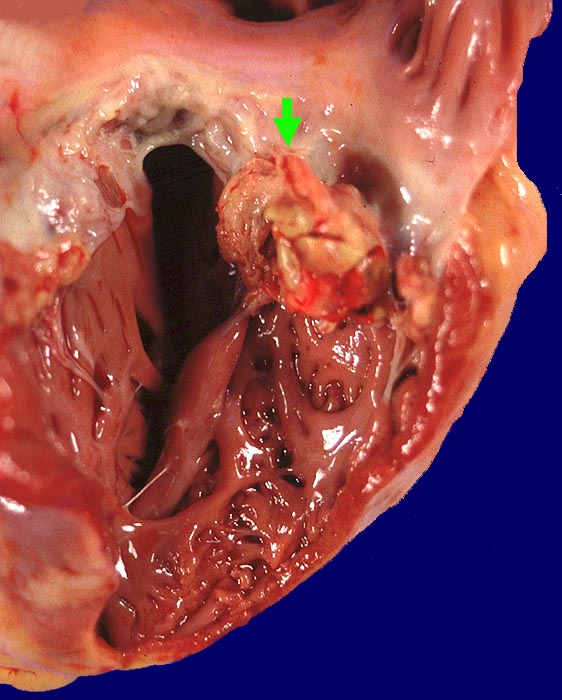

Makroskopisch sind entweder flache rötliche fibrinbelegte Ulzera (=ulcerosa (> 2935)) oder zusätzlich weiche gelbbraune bröcklige erbs- bis pflaumengrosse Polypen (=ulceropolyposa (> 2936) (> 8376)) oder ausschliesslich polypoide Fibrinbeläge (=marantica) auf einem Endokarddefekt oder einer partiell zerstörten Klappe erkennbar.

• Längsschnitt durch Aorta, Aortenklappe und linkes Ventrikelmyokard.

• Oben im Bild die Aorta mit kleinem Fibroatherom.

• Abszedierende Entzündung der aortalen Adventitia ausgehend von septikopyämischen Streuherden.

• Ulzerierte Aortenklappe(ulcerosa).

• Dem ulzerierten Klappengerüst aufgelagerte polypöse Vegetation aus Fibrin und Granulozyten durchsetzt von blauen Kokkenbakterienkolonien (polyposa).